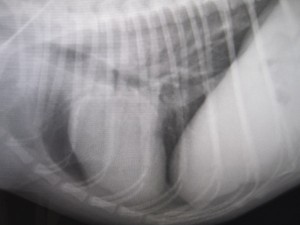

内視鏡で異物を除去してる所です。

ジャーキーが滞留しているのがわかります。